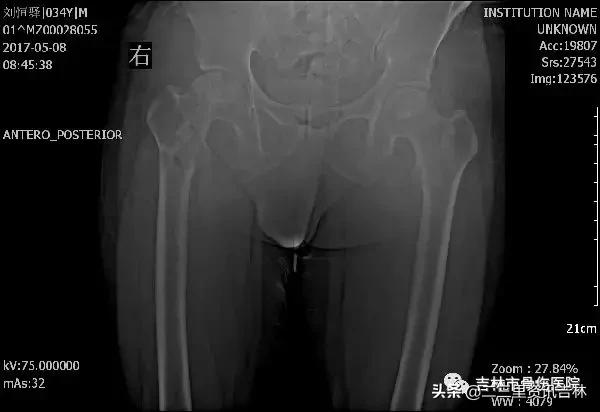

该患于2008年6月因“右股骨颈骨折”在外院行“右侧髋关节置换术”,术后恢复良好,休养至今,于2016年11月30日在自家走路时不慎滑倒摔伤,伤后出现右髋部肿痛,不敢活动,未经处置,在家休养至今未见缓解,现为求系统治疗前来我院就诊,经门诊医生查体拍片后以:“右侧髋关节置换术后假体周围骨折”收入院。

患者入院后给予常规检查,经三级医师查房,临床诊断确诊,查无明显手术禁忌症后在腰硬+全麻麻醉下行“右侧髋关节置换术后假体周围骨折关节翻修术”,术后抗感染、消肿、抗凝、关节功能松动练习等对症治疗,术后患者恢复良好。